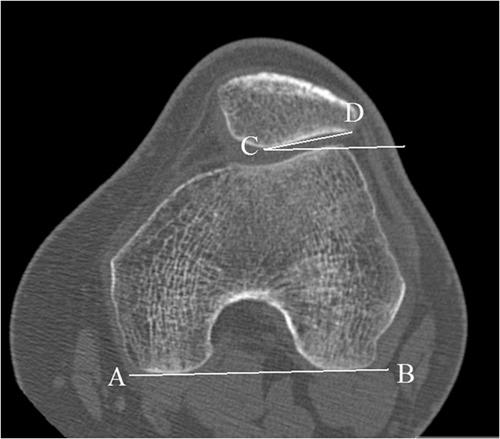

Physical examination and imaging evaluation including standard radiographs are crucial in identifying evidence of malalignment or instability. Magnetic resonance imaging provides valuable information about concomitant soft tissue injuries to the medial stabilizers as well as injuries to the articular cartilage, including chondral shears and osteochondral fractures. Quantitative magnetic resonance imaging assessing the ultrastructure of cartilage has shown high correlation with histology and may be useful for timing surgery.

Evaluation of patellofemoral disorders is complex and requires a comprehensive assessment. Recent advancements in imaging have made possible a more precise evaluation of the individual anatomy of the patient, addressing issues of malalignment, instability, and underlying cartilage damage.